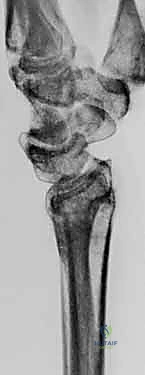

- الأشعة السينية الرقمية (X-rays): للرسغين السليم والمصاب، لمقارنة الزوايا وحساب مقدار التشوه بدقة.

- الأشعة المقطعية (CT Scan) مع إعادة البناء ثلاثي الأبعاد (3D Reconstruction): هذه الخطوة حاسمة. تتيح للدكتور هطيف رؤية العظم من جميع الزوايا، وتحديد مكان القص بدقة متناهية.